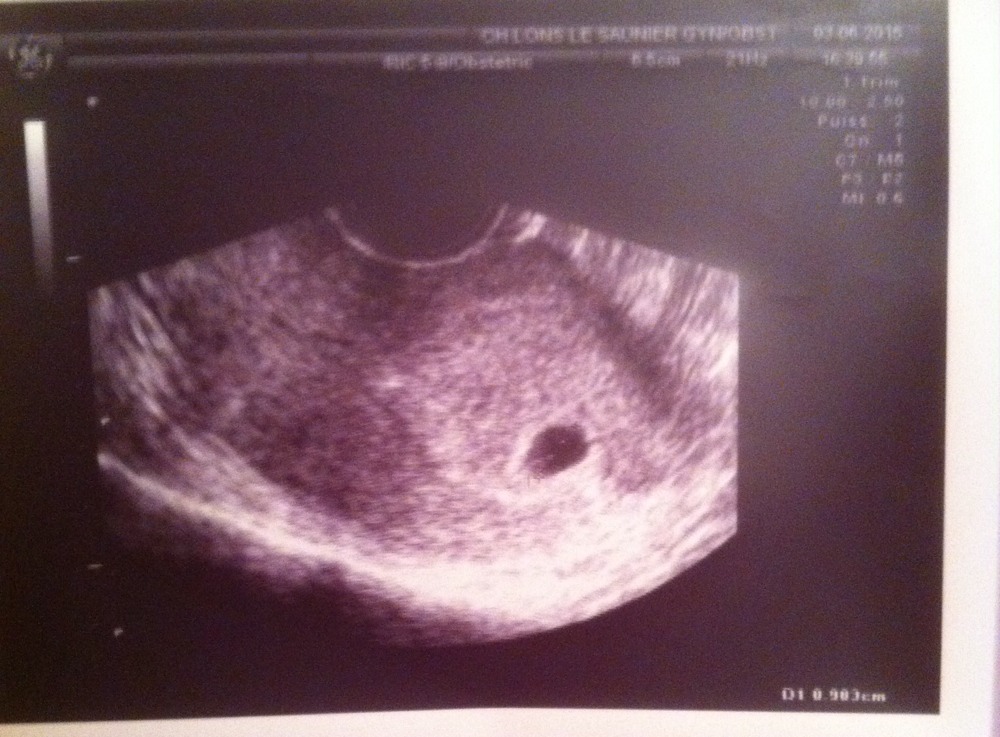

L'échographie est un examen basé sur l'utilisation d'ultrasons pour visualiser les évolutions du bébé dans le ventre de la mère et permet de détecter d'éventuelles anomalies. Cet examen, indolore et sans danger pour le petit, est très important pour le suivi de la grossesse. Généralement, lorsqu'une grossesse se déroule.. Pour une 5ème semaine de grossesse, l'examen par échographie révèle la présence de la vésicule vitelline. Il s'agit d'une zone nutritive indispensable au développement de la vie. C'est un élément qui apparait pour la création des premiers globules rouges et des cellules sexuelles. La vésicule n'est plus visible par la suite.

Échographie à la 5e semaine de grossesse (21 photos) taille du fœtus, ce que l’on peut voir et

Anatomie échographique d'une grossesse de 6 SA